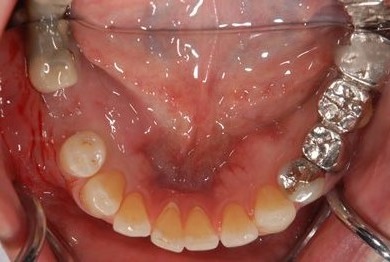

骨再生スピードインプラント治療+セラミック治療

| 治療方針 | 骨再生法によりインプラント治療を可能にする。抜歯と同時にインプラント埋入を行い、治療期間を短縮する。 | ||||||||||||||||||||||||||||||||

| 治療内容 | インプラント3本(抜歯即日スピードインプラント、GBR)、メタルボンドセラミッククラウン4本 | ||||||||||||||||||||||||||||||||